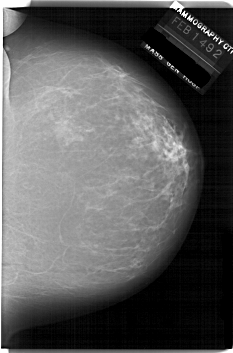

A_1940_1.LEFT_MLO

LEFT_MLO LINES 6541 PIXELS_PER_LINE 4891 BITS_PER_PIXEL 12 RESOLUTION 43.5 OVERLAY